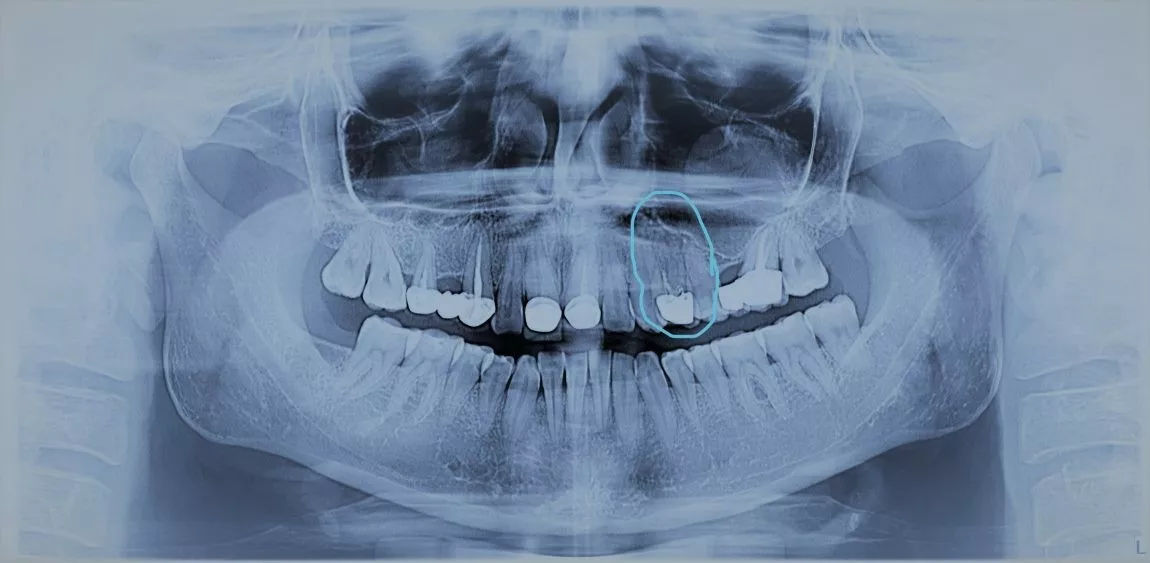

Comparație radiografie 2D – 3D

Un alt exemplu este identificarea mărimii unui granulom. În funcție de mărimea acestuia, tratarea afecțiunii se rezolvă edodontic sau chirurgical.

Localizarea structurilor anatomice, măsurarea arcadelor, depistarea rapidă a leziunilor sau a formațiunilor anormale sunt doar câteva dintre avantajele analizei digitale dentare.